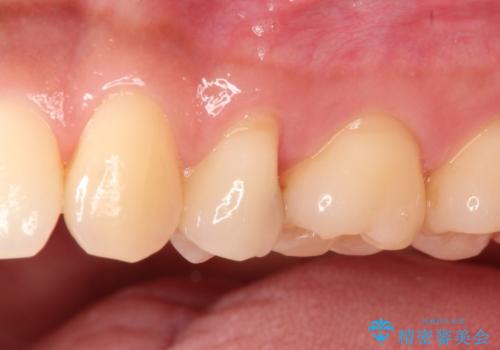

適合の良いセラミックインレー

e-max プレスインレーにて修復治療を行っているため適合性及び審美性の高い治療を行うことができます